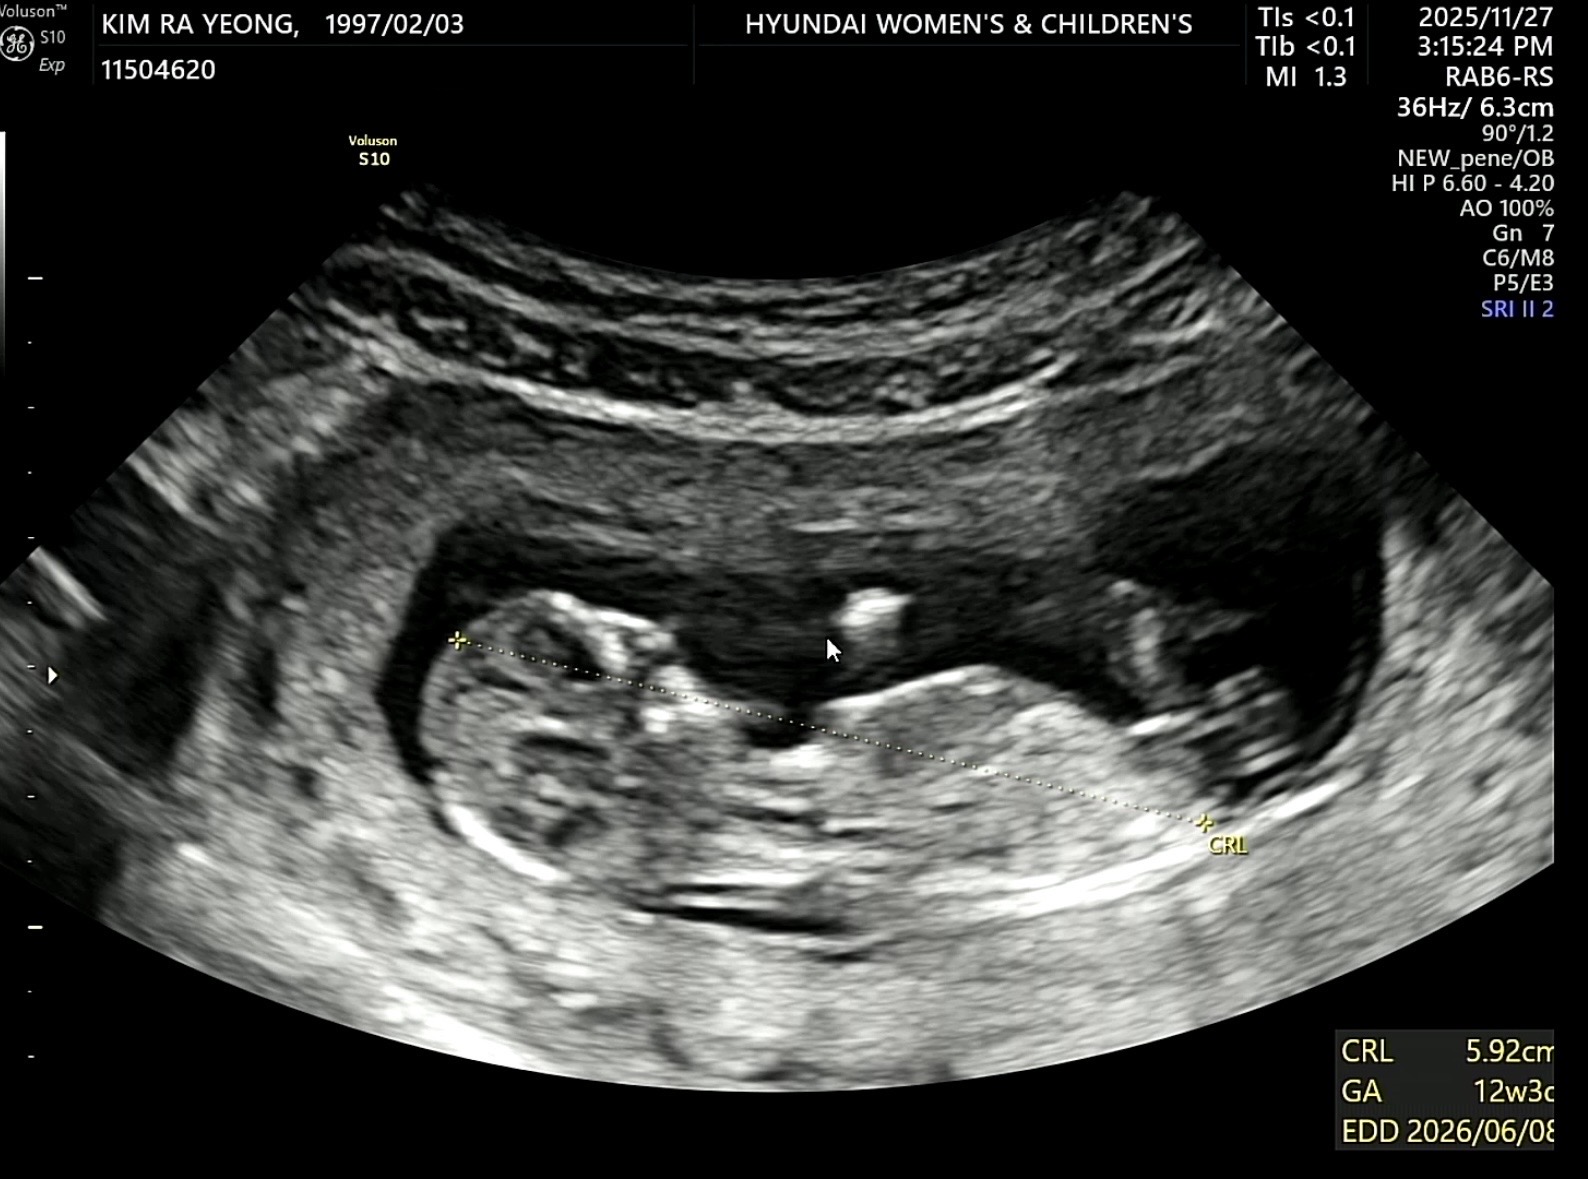

각도법 부탁드립니다!!

아직 12주 2일차 사진인데 다리사이가 매끈하니까 원장님이 51%는 딸로 생각할수 있겠다 하셨는데 다음달에 가면 🌶️가 생길수도 있을까요?? 마구마구 참견 부탁드려요!!🙏🙏